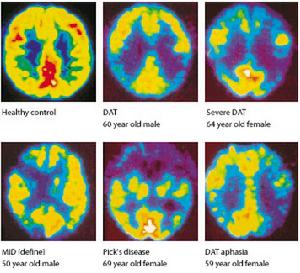

痴呆的早期表現一般不甚明顯處於這一階段的患者往往只是感到思維不如以前敏捷用腦後容易感到疲勞對於不熟悉的業務或內容比較複雜的任務感到吃力對於有時間限制要按期完成核心的作業更是覺得力不從心除此之外並無其他異常對於早已習以為常的任務一般仍能應付不顯困難到症狀充分發展的階段便會出現以下幾個影像方面的改變:

痴呆1.認知功能測驗及智力測驗:痴呆篩選測驗有Folstein(1975)創用的簡易智力狀態檢驗(MMSE)、 長谷川和夫(1974)創用的長谷川痴呆量表(HDS)、PATTIE等(1979)創作的認知量表(CAS)等。這些測驗的共同特點是內容較簡單,能在較短時間內完成,一般都設成痴呆的劃界分,因此頗為實用。以MMSE為例,若得分〈15分這痴呆,15~24分為可能痴呆。韋氏成人智力測驗只有病前做過的患者尚可使用,否則難度較大。

4.實驗室檢查:疑有器質性痴呆的患者應在選擇性作腰椎穿刺,血液生化檢驗,腦電圖,腦超音波,同位素腦掃描,頭顱X線平片,氣腦造影,腦血管造影或CT等檢查。